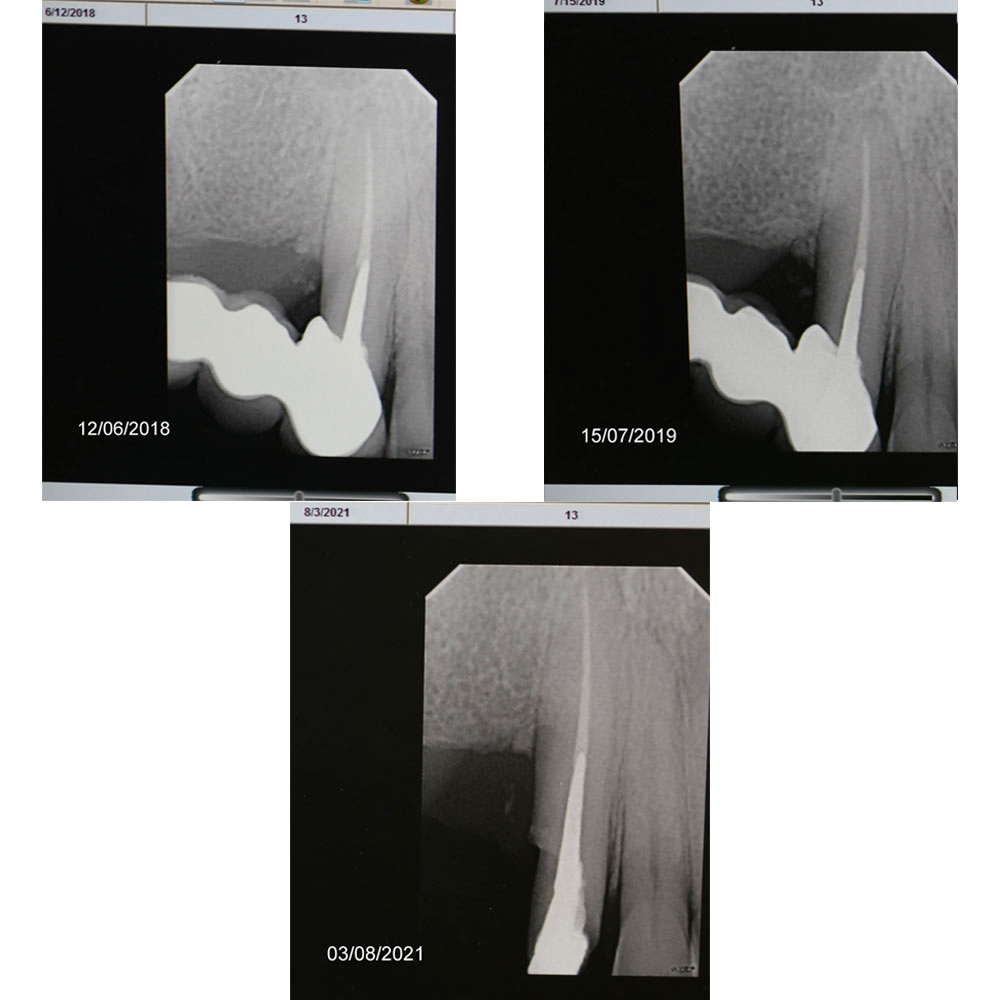

Rare documented case from 2017 to 2021 - bone regrowth after cleaning, curretage and applying DSI Syntoss Plus

Dear colleagues, I would like to share a clinical case that I have been observing since 2017. A patient came to the clinic with complaints of swelling and pain in the area 1.3, 1.4, 1.5. Conservative therapy was suggested, and after dealing with the acute period, a surgical procedure including cleaning of the periodontal pocket, scaling and root planing and filling the bone pocket with DSI Syntoss Plus that contains beta-tricalcium phosphate granules. The procedure was performed in 2017, the old bridge was replaced with a new one, which is fixed with temporary cement for regular revision due to the unstable condition of 2.6. The patient is unable to undergo implantation for a number of reasons, so the 2.6 will be kept until the last possible moment. Its mobility is grade 2 and the condition of the mucosa can be seen in the photo. The whole process of bone maturation is shown on the x-rays. Thank you for your attention.